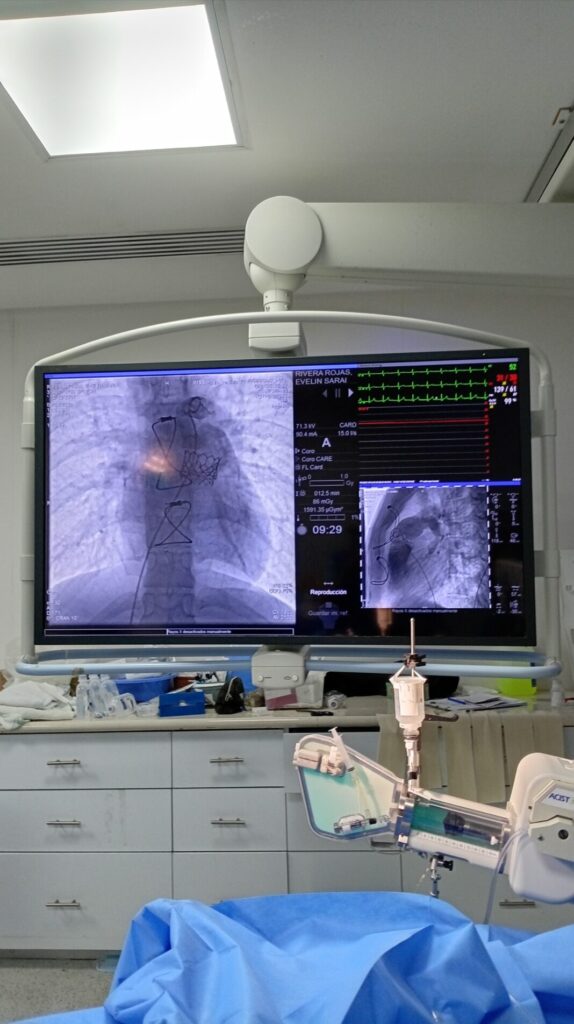

Con una técnica de mínima invasión, médicos especialistas logran salvar a dos jóvenes con procedimientos de menos de una hora.

En un avance que marca un antes y un después para la medicina en el norte de México, la UMAE No. 71 del IMSS en Torreón ha logrado sustituir las traumáticas cirugías a corazón abierto por una técnica mucho más humana y eficiente: la implantación de válvulas a través de una pequeña punción en la ingle.

Esta proeza médica benefició a Evelin y Luis, dos jóvenes de 18 y 19 años que padecían Tetralogía de Fallot, un defecto congénito que solía condenar a los pacientes a múltiples intervenciones quirúrgicas de alto riesgo. Gracias a este procedimiento transcatéter, ambos pudieron evitar el quirófano tradicional, recuperándose en apenas 48 horas.

• Precisión quirúrgica: A través de la vena femoral, los médicos navegaron hasta el corazón para colocar la prótesis sin necesidad de abrir el tórax.